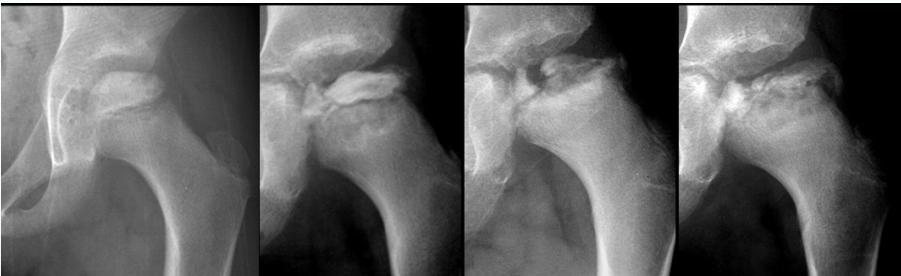

Imaging:

- Required views: AP and Frog lateral pelvis

- Key finding: Slippage of femoral epiphysis

Radiographic Examples:

Comparative views showing slipped vs. normal hip:

(Source: Apley’s System of Orthopedics and Fractures)

X-ray Diagnosis:

| View | Slipped Hip | Normal Hip |

|---|---|---|

| AP | ![]() | - |

| Frog Lateral | ![]() | - |